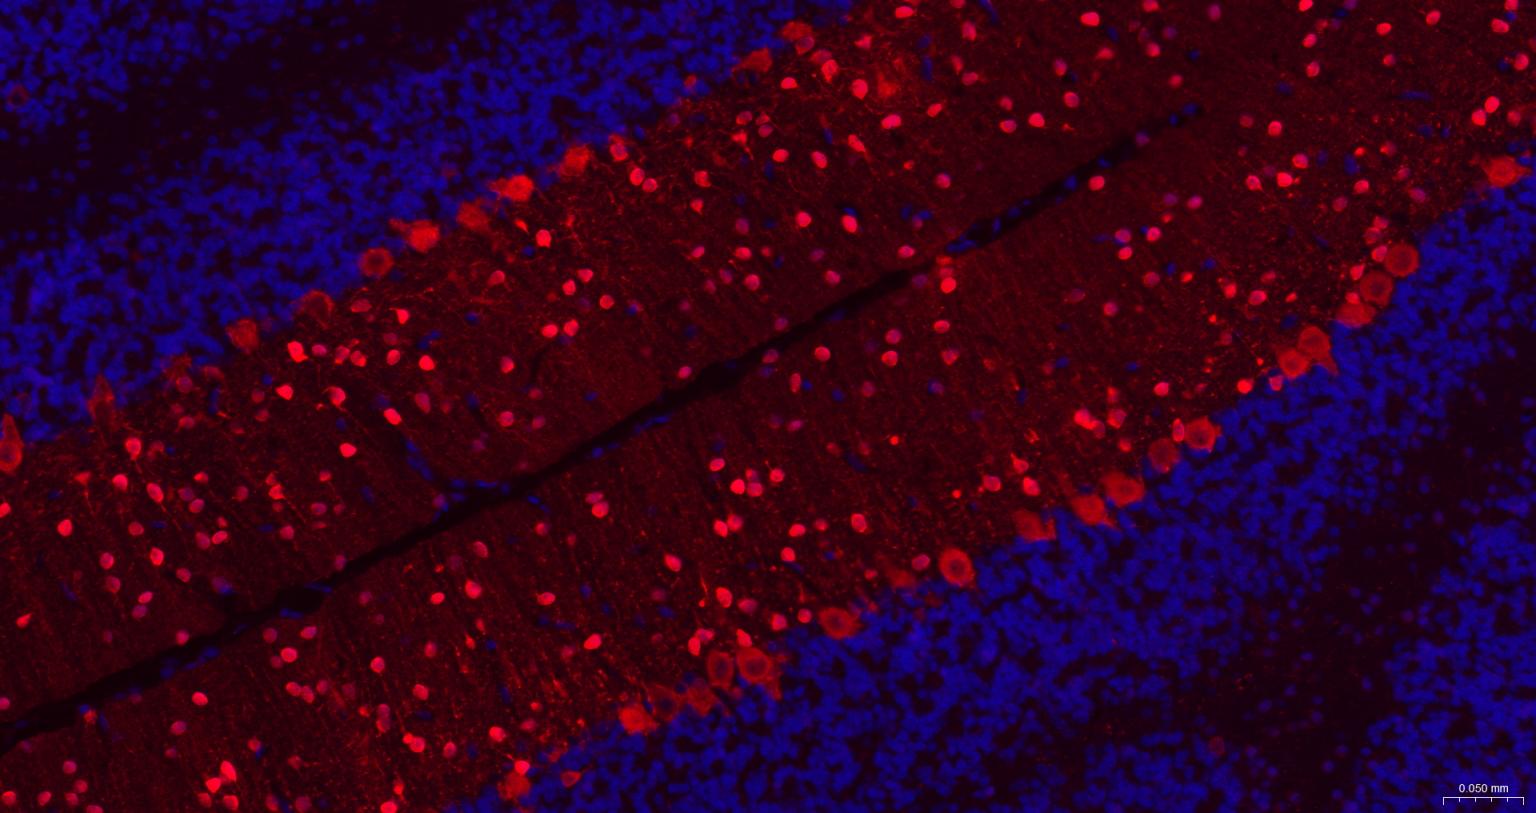

Paraformaldehyde-fixed, paraffin embedded Mouse Cerebellum; Antigen retrieval by boiling in sodium citrate buffer (pH6.0) for 15 min; The section was incubated with Parvalbumin Monoclonal Antibody, Unconjugated (bsm-61405R) at 1:200 overnight at 4°C. Followed by conjugated Goat Anti-Rabbit IgG antibody (Red, bs-0295G-BF594), DAPI (blue, C02-04002) was used to stain the cell nuclei.

Paraformaldehyde-fixed, paraffin embedded Rat Cerebellum; Antigen retrieval by boiling in sodium citrate buffer (pH6.0) for 15 min; The section was incubated with Parvalbumin Monoclonal Antibody, Unconjugated (bsm-61405R) at 1:200 overnight at 4°C. Followed by conjugated Goat Anti-Rabbit IgG antibody (Red, bs-0295G-BF594), DAPI (blue, C02-04002) was used to stain the cell nuclei.